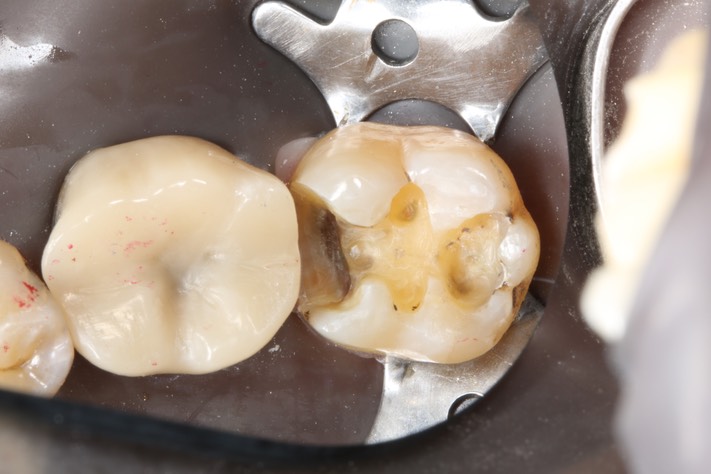

Alan Tamashiro #18 caries removal